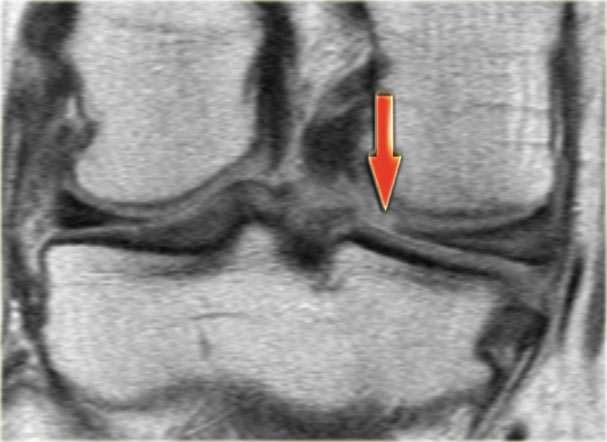

Chúng ta bắt đầu với lát cắt ở giữa của khảo sát.

Lưu ý thân sụn chêm bên có kích thước nhỏ với hình dạng bất thường (mũi tên xanh).

Phần bờ trong bị khuyết được nhìn thấy ngay phía ngoài dây chằng chéo trước (mũi tên đỏ). - Phần sụn chêm bị rách di lệch vào trong, tức là phần quai xách, có thể được theo dõi theo hướng ra sau trong hố gian lồi cầu.

- Tiếp tục.

- Đây là điểm nối giữa phần quai xách và sừng sau.

- Đây là lát cắt phía trước cho thấy một nang sụn chêm.

- Lưu ý tín hiệu cao theo chiều ngang.

- Tại đây chúng ta có thể nhận thấy sự phức tạp của tổn thương rách sụn chêm với thành phần theo chiều dọc và chiều ngang (các mũi tên).